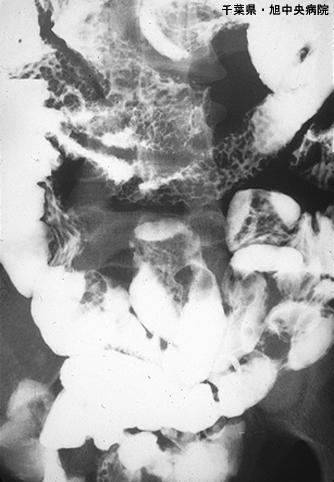

Amiloidosis del Intestino Delgado acompañada de ulceración y mucosa rugosa de tipo erosiva (Caso presentado por Hospital Central de Asahi, Prefectura de Chiba)

Enfermedad Inflamatoria - Ulcerativa/Amiloidosis del Tubo Digestivo

intestino delgado/mas de dos

Rayos X